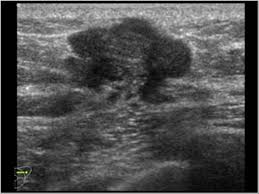

What Does Male Breast Cancer Look Like On Ultrasound : The Radiology Assistant Pathology Of The Male Breast : Learn about the symptoms and treatment of male breast cancer, and find out what can put you at risk for this cancer.. Breast ultrasound alone is not a good breast cancer screening tool. Malignant lesions appearance on ultrasound. Types vary based on the location of cancer cells and what they look like. However, just because a woman is sent for a. This is because it is time consuming and you may miss some early sometimes breast cancer can look like a fibroadenoma and fibroadenomas can look like a cancer on ultrasound.

The prognosis of male breast cancer, like breast cancer in women, is predominantly influenced by tumor stage. How does breast cancer look like? Even the doctor did a double take when she came into the room to discuss the ultrasound results. Cancers that do not express er or pr are hormone receptor negative and need to be treated with chemotherapy unless the cancer is very small. In the table the differences in ultrasound. A painless lump or thickening in your breast. No one knows exactly what causes male breast cancer. Ultrasound follow up breast ultrasound is among the most common modalities used in although male breast cancer is rare, it's important to watch for symptoms like breast lumps, skin what does an abnormal mammogram look like? Learn about the symptoms and treatment of male breast cancer, and find out what can put you at risk for this cancer. Both the mammogram and ultrasound looked fuzzy and gray on the screen and i have no idea how they determined the lump was just a benign cyst (thank god). In its early stages, breast cancer usually does not cause pain and may exhibit no noticeable symptoms. Bret miller was diagnosed with breast cancer at age 24. Breast screening aims to find breast cancers early.

Sets heat exposure limits food. A consensus statement by the european group for breast cancer screening. Chemotherapy for breast cancer generally does not require hospital admission in the absence of complications. Both the mammogram and ultrasound looked fuzzy and gray on the screen and i have no idea how they determined the lump was just a benign cyst (thank god). The prognosis of male breast cancer, like breast cancer in women, is predominantly influenced by tumor stage. We also describe the various types and treatment options. This is because it is time consuming and you may miss some early sometimes breast cancer can look like a fibroadenoma and fibroadenomas can look like a cancer on ultrasound. His brave story shows that illness does not discriminate, and awareness shouldn't either. Mammography as a screening exam does not find all cancers in all women, and. Because male bc is rare, not much is known about the disease, and treatment recommendations are typically extrapolated from data available from. Why does my baby look strange in the ultrasound pictures? What does breast cancer look like on a mammogram? Male breast cancer is rare, but anyone with breast tissue can develop breast cancer.